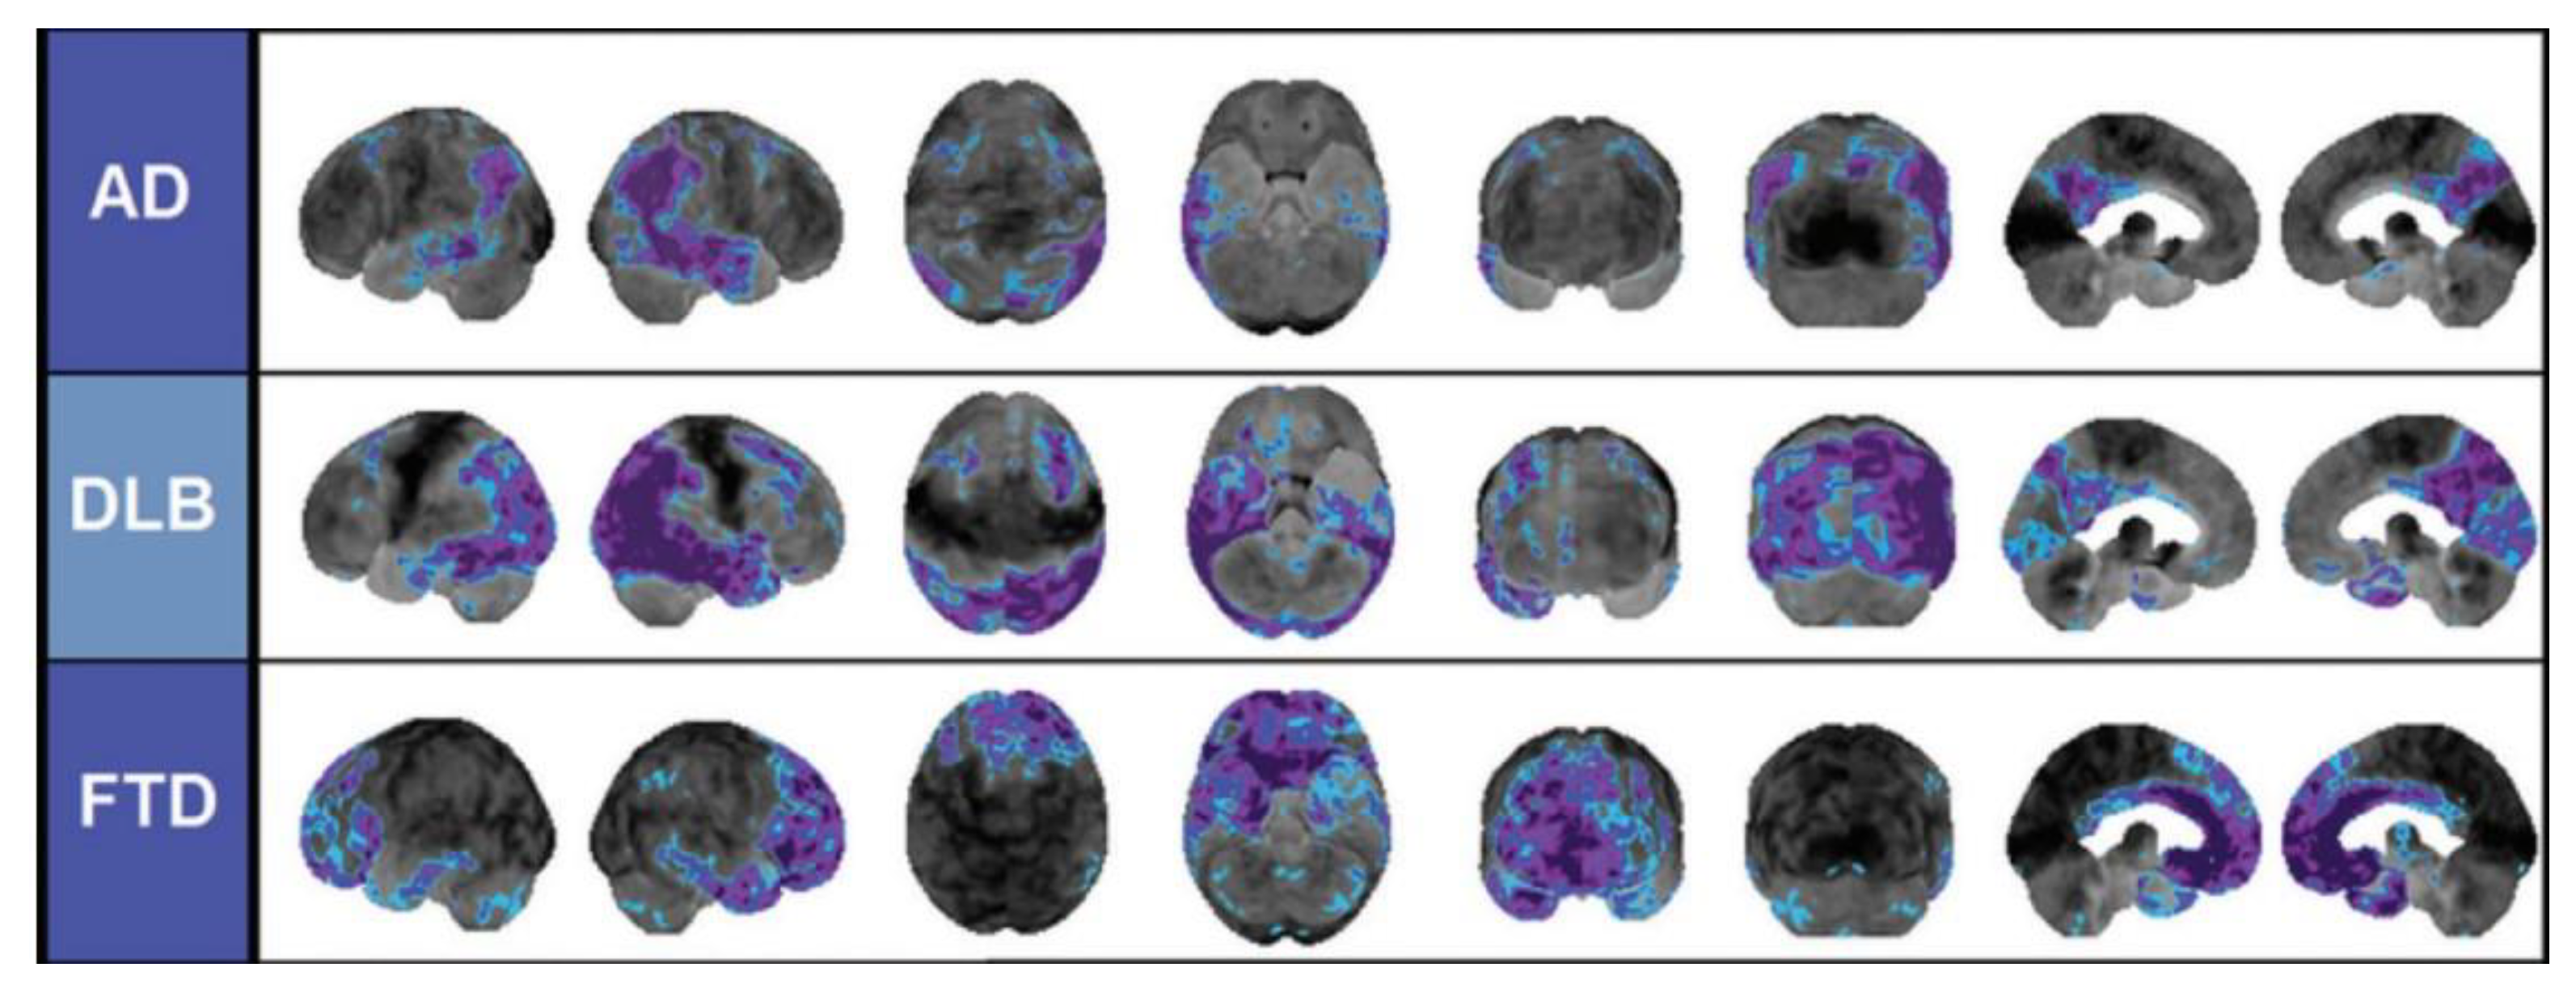

- Roy, R.; Niccolini, F.; Pagano, G.; Politis, M. Cholinergic imaging in dementia spectrum disorders. Eur. J. Nucl. Med. Mol. Imaging 2016, 43, 1376–1386. [Google Scholar] [CrossRef]

- Brown, R.K.J.; Bohnen, N.I.; Wong, K.K.; Minoshima, S.; Frey, K.A. Brain PET in Suspected Dementia: Patterns of Altered FDG Metabolism. Radiographics 2014, 34, 684–701. [Google Scholar] [CrossRef] [PubMed]